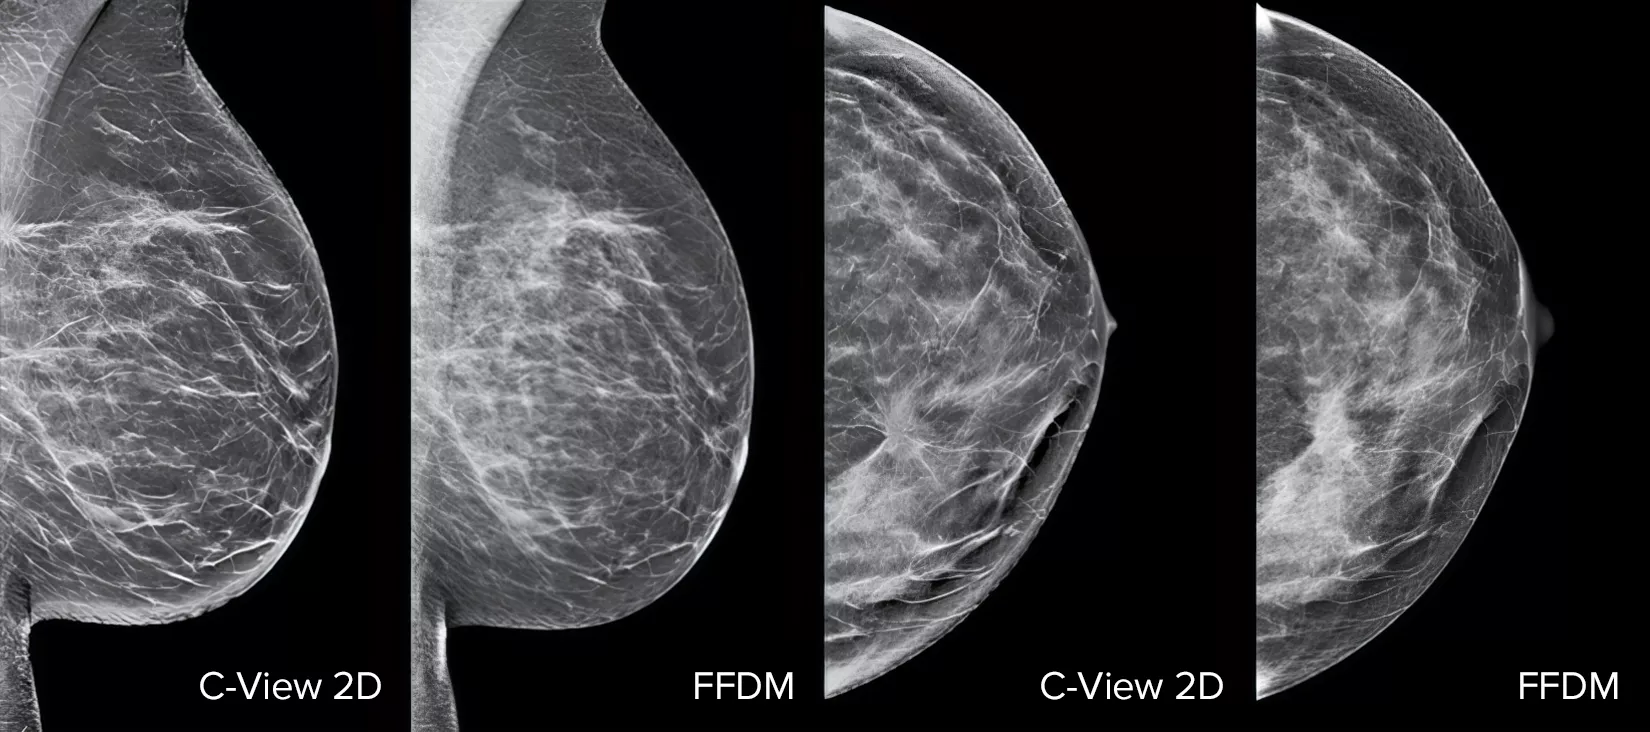

Architectural distortions, mass lesions, and bright spots commonly found in microcalcifications are more visible in the C-View 2D image than on the traditional FFDM 2D images or tomo slices.4,6-9

The Proof is in the Details

C-View 2D images are clinically proven3,5 and FDA approved to diagnostically replace the FFDM images within a tomosynthesis screening exam. The images are also a navigational aid to the tomosynthesis slice review. Published studies show that the low dose 3D Mammography exam finds invasive cancer earlier, while also reducing false positive recall rates compared to 2D alone.4,5,7

Architectural distortions, mass lesions, and bright spots commonly found in microcalcifications, are more visible in the C-View 2D image than on the traditional FFDM 2D image or tomo slice.4,6-9

C-View 2D vs FFDM breast x-ray images